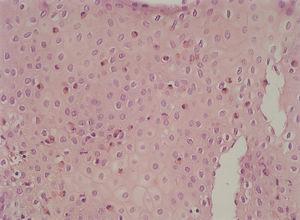

La anatomía patológica mostraba en todos los pacientes presencia de eosinófilos en mucosa esofágica en número superior a 20 por campo de gran aumento, de predominio peripapilar, así como hiperplasia epitelial (fig. 4). En 5 casos (45,45 %) se encontró un recuento aumentado de eosinófilos en antro gástrico y segunda porción de duodeno, por lo cual se realizó con posterioridad fibrocolonoscopia. En todos ellos se observaba una eosinofilia mucosa por encima de los valores normales en íleon terminal, colon y recto-sigma, que fue diagnosticada de gastroenteropatía eosinofílica con afectación generalizada (fig. 5).

Figura 4. Infiltrado eosinofílico intraepitelial característico de esofagitis eosinofílica, en cantidad superior a 20 eosinófilos/campo de gran aumento. (Hematoxilina-eosina, x40.)